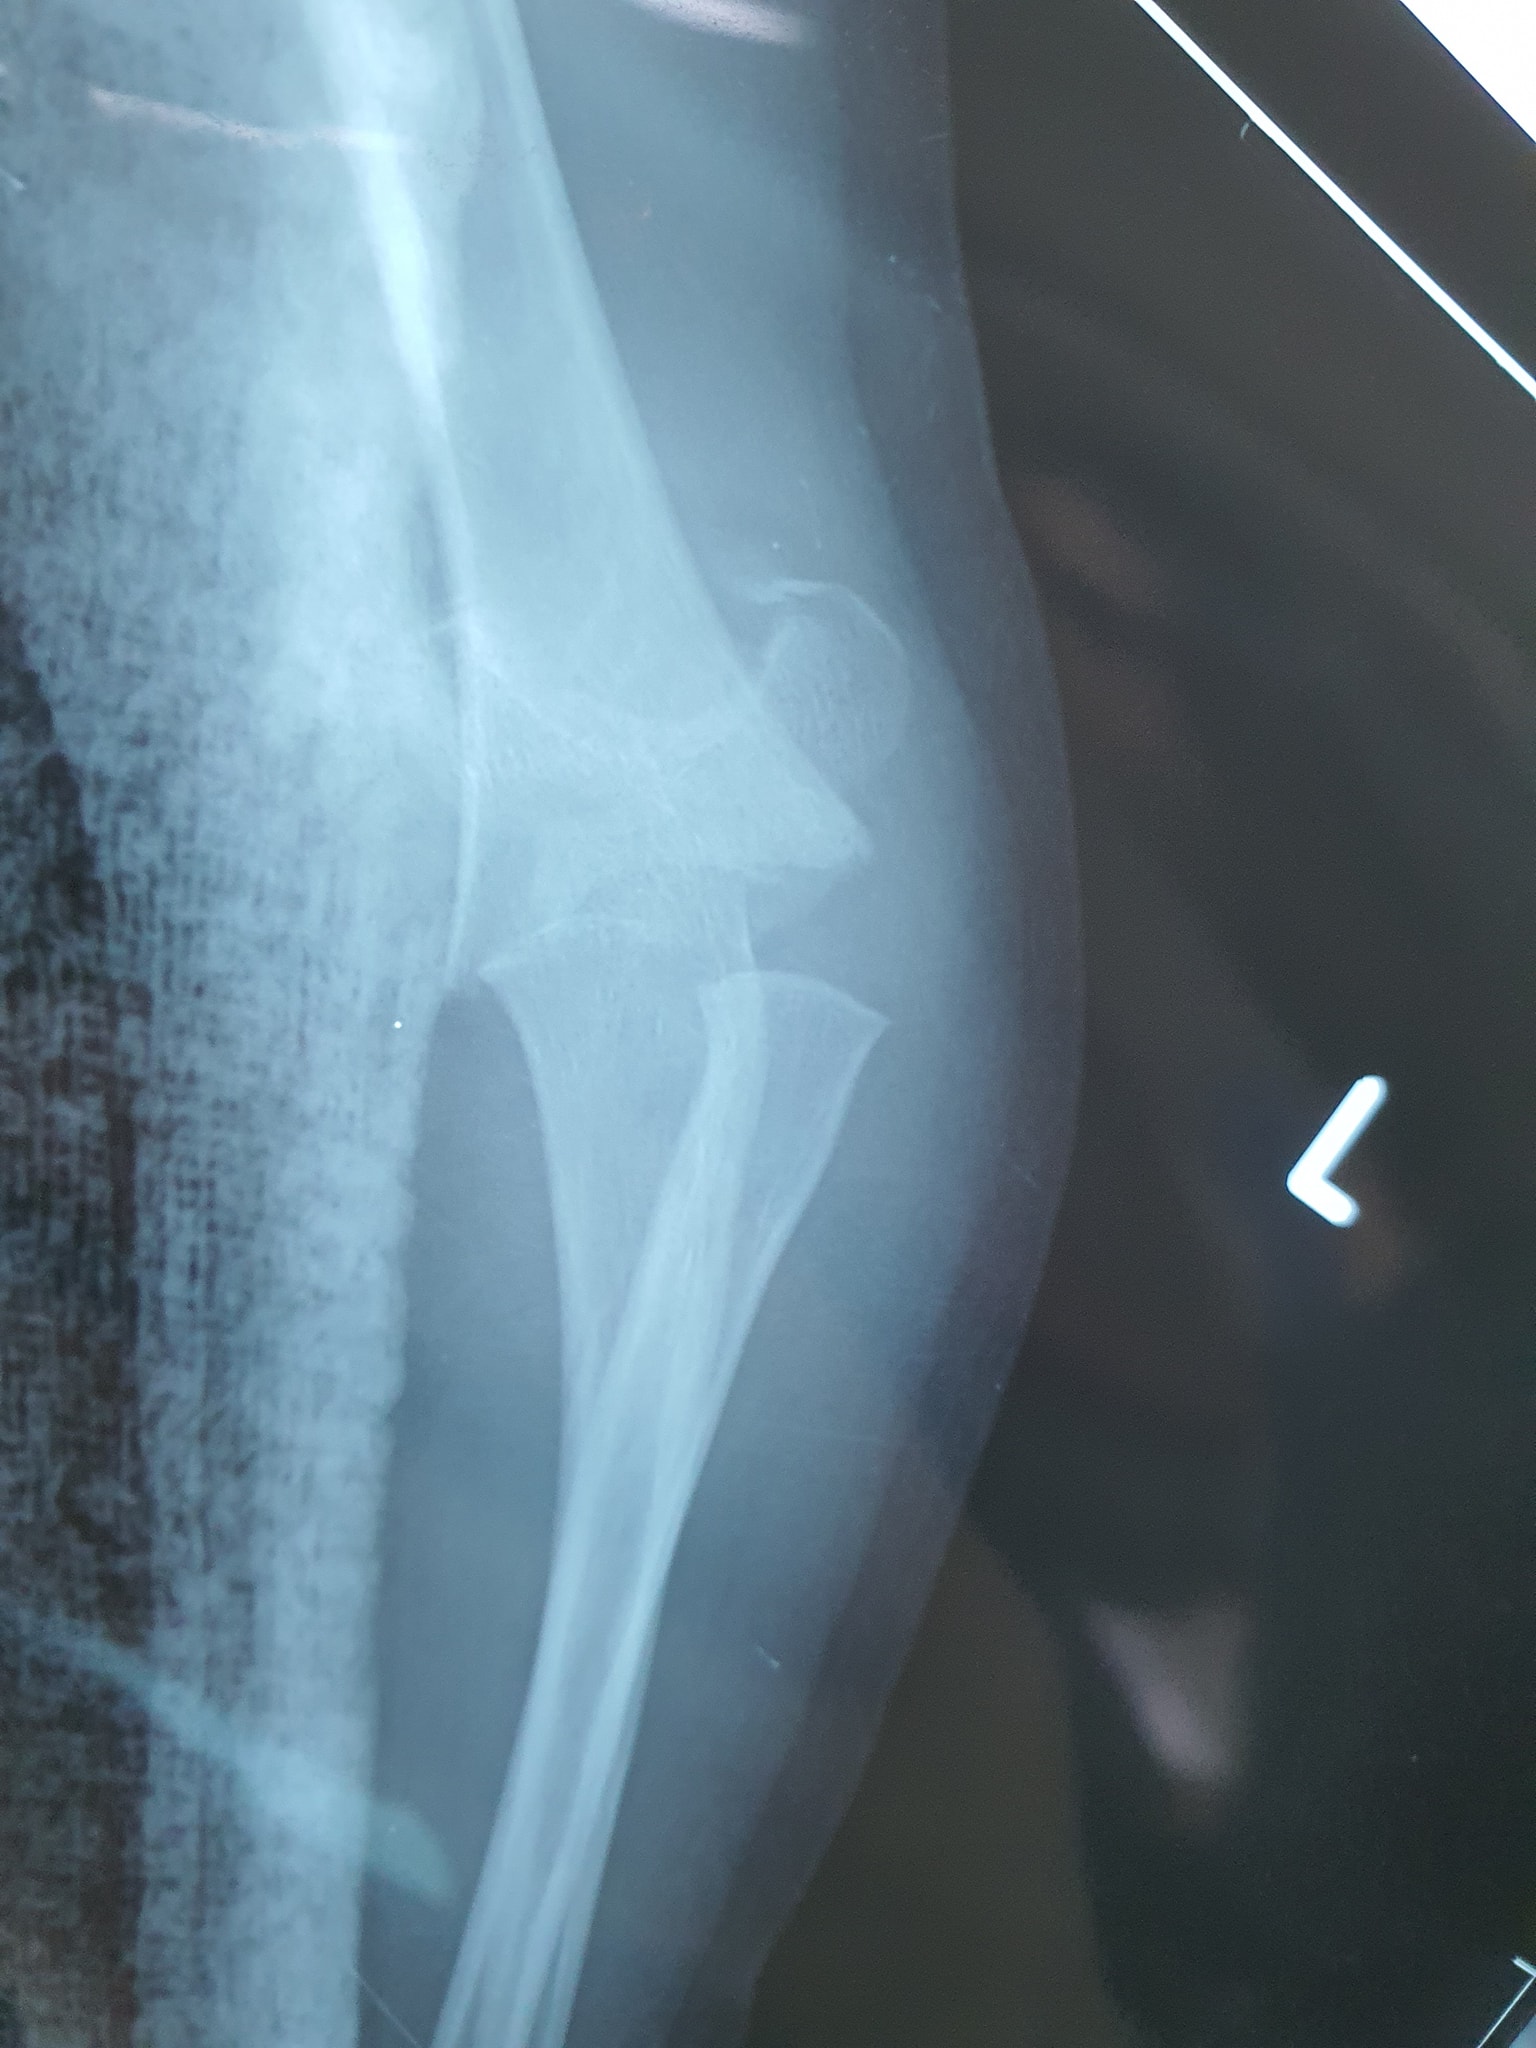

كافة انواع الكسور وعلاجها